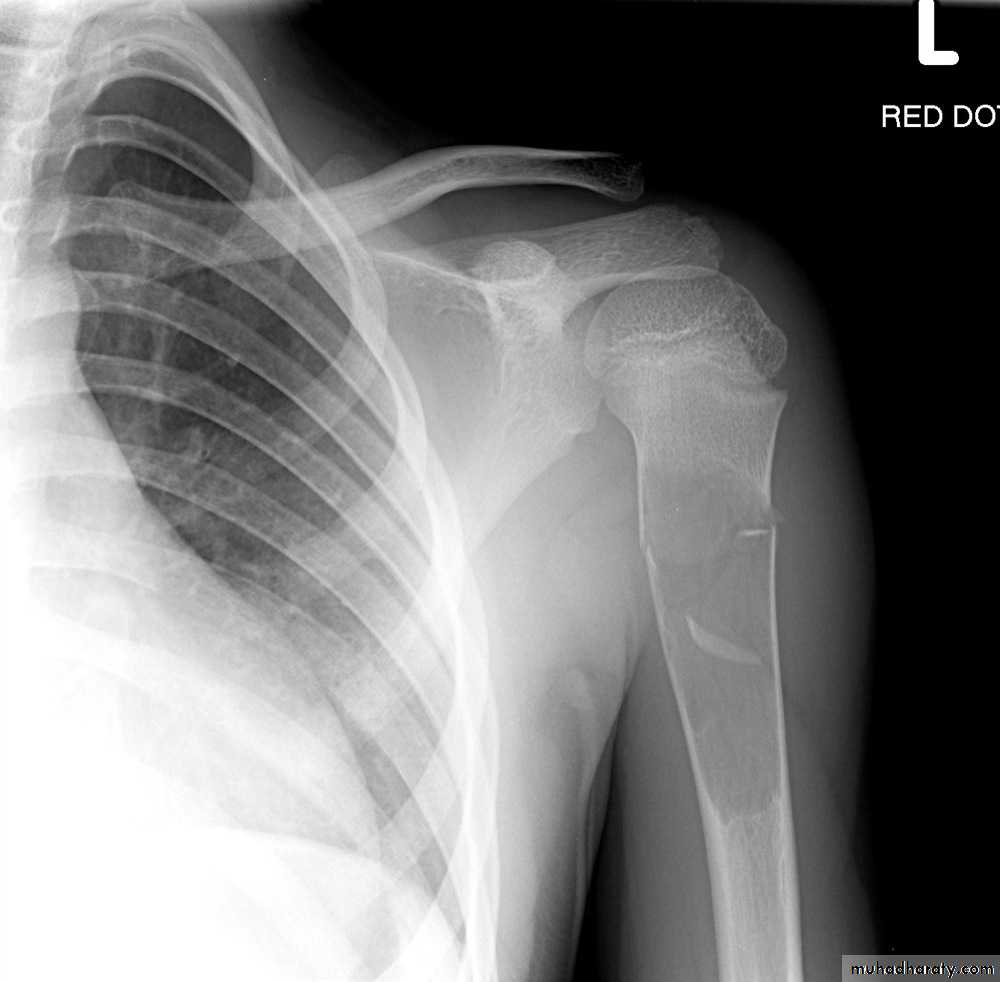

Mushroom Deformity of the femoral neck in perthes disease

being flattened femoral head with a contiguous broad neck, accompanied by awidened articular space .Fallen fragment sign